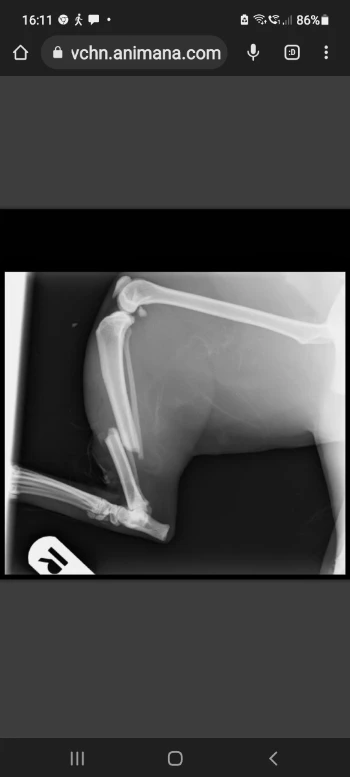

• Hallo iedereen. Ik ben Nala een ontzettend lieve poes van 3 jaar oud. Ik ben overgenomen door mijn baasje omdat de vorige eigenaar mij niet meer wilde die had een ander 'speeltje' gevonden, een herdershond en toen moest ik weg. Ik ben aangereden en heb 2 botten gebroken in mijn rechterachterpoot. De dader is onbekend. Mijn baasje ging met mij op zondagmorgen naar de dierenarts. Ik ben geopereerd en heb een plaatje met schroeven erin gekregen met antibiotica. Het gaat hartstikke goed met mij na 6 weken in de bench en ben lekker verwend. Maar mijn baasje zit nog met de rekening van 948,65. Ook wil zij nu de tuin voor mij afzetten zodat er niets meer met mij kan gebeuren. Dit gaat zij van haar vakantiegeld doen. Zij verwacht niet het hele bedrag hier 'te krijgen' maar met elke 5,= zou zij heel blij zijn.